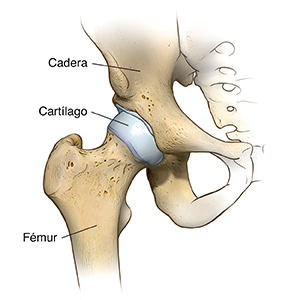

El reemplazo de cadera (artroplastia total de cadera) es una cirugía que se hace para reemplazar una articulación de la cadera que se ha desgastado o dañado. El cirujano reemplaza la articulación vieja con una articulación artificial (prótesis). Esta cirugía puede ser recomendable después de una fractura de cadera o si tiene dolor intenso causado por artritis.

Osteoartritis. Esta es una enfermedad degenerativa de las articulaciones que afecta a la mayoría de los adultos de mediana edad y mayores. Puede producir la desintegración del cartílago articular y del hueso adyacente en las caderas.

Artritis reumatoide. Este tipo de artritis causa inflamación en la membrana sinovial de la articulación. Esto genera líquido sinovial extra y la destrucción de la articulación, y puede causar dolor intenso y rigidez.

Artritis traumática. Este tipo de artritis es causada por una lesión. A su vez, puede dañar el cartílago de las caderas.

La osteoartritis causa la pérdida de cartílago articular en la cadera. El daño en el cartílago y los huesos limita el movimiento y puede causar dolor. Las personas con dolor intenso debido a la enfermedad articular degenerativa pueden ser incapaces de realizar actividades normales que requieren inclinarse al nivel de la cadera, como caminar o sentarse.